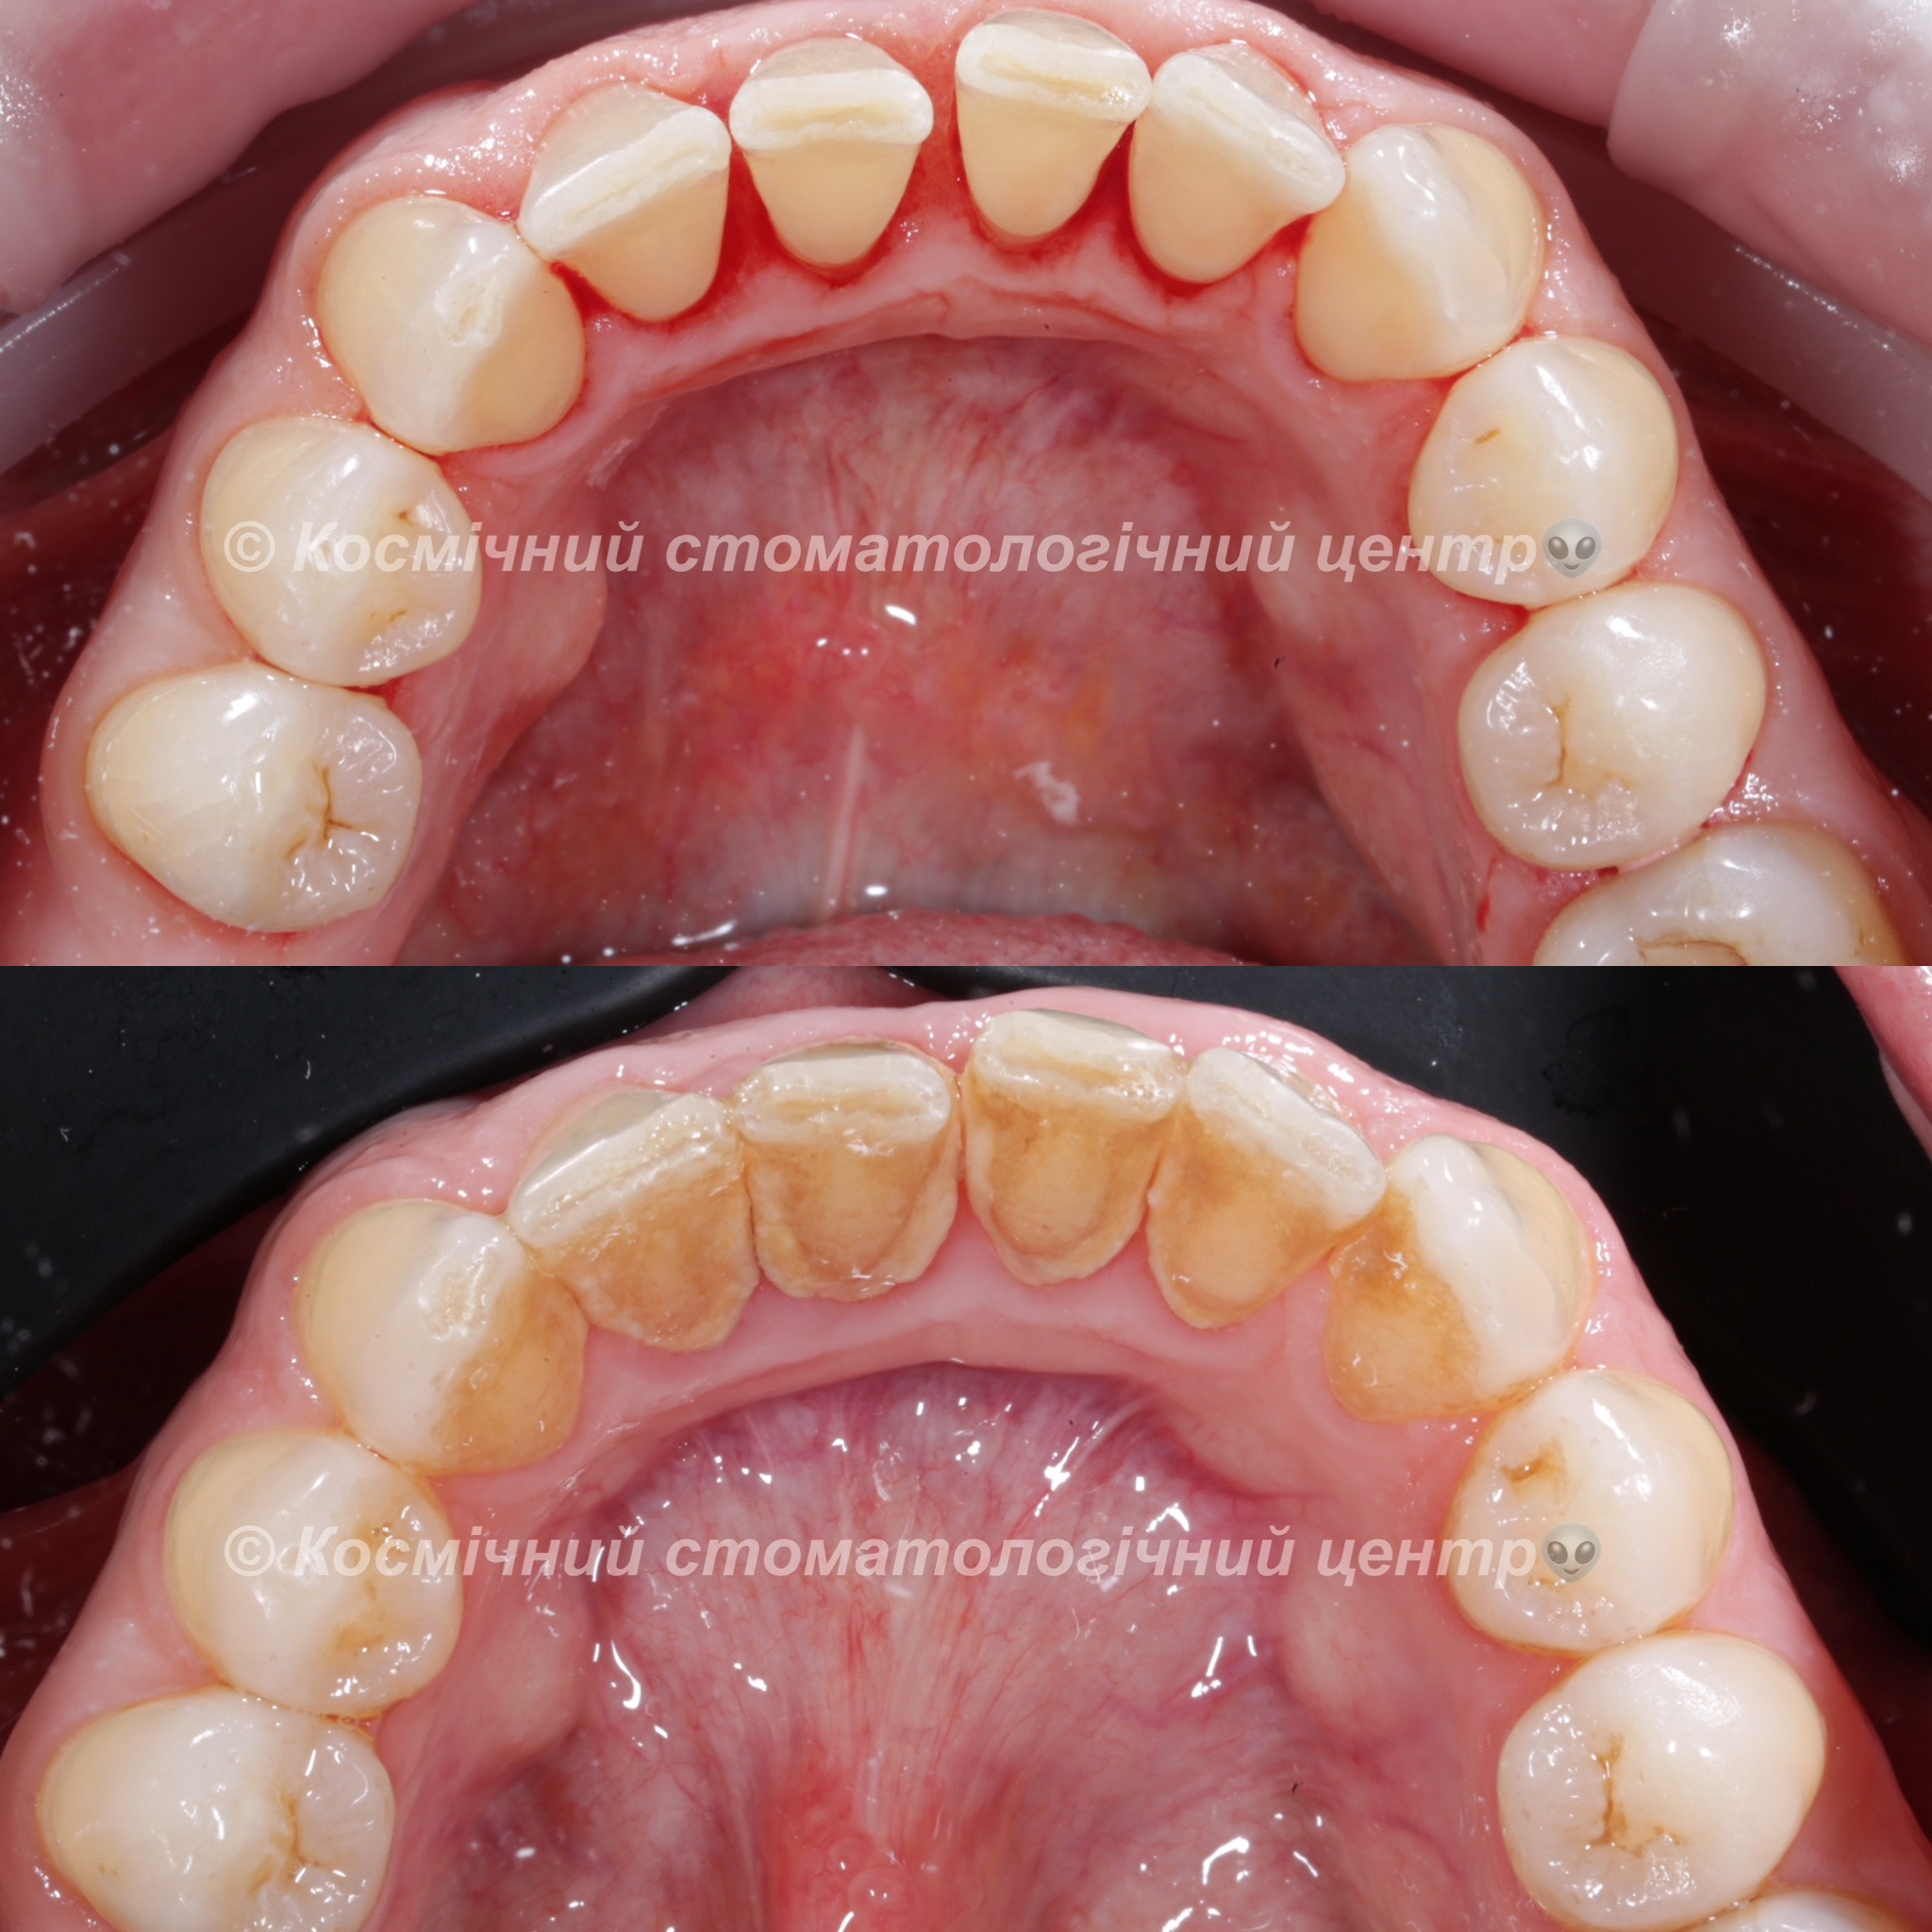

Професійна гігієна (чистка) зубів складається з кількох етапів

• Комп'ютерна анестезія у разі підвищеної чутливості зубів.

• Зняття каменю ультразвуковим девайсом SIRONA (Німеччина) та звуковим наконечником KAVO (Німеччина) з електронним регулюванням потужності.

• Зняття каменю у важкодоступних місцях пародонтальними кюретами HU-Friedy.

• Зняття нальоту гігієнічними перлинами KaVo PROPHY pearls SUPRAGINGIVAL CALCIUM CARBONATE в індивідуальних пакуваннях із ароматом на вибір: персик, апельсин, м'ята, чорна смородина та нейтральний смак.

Ультразвукова чистка зубів

Зубний камінь, в залежності від місця утворення, поділяється на над- та підясенний. Найбільшу небезпеку для здоров'я зубів становить другий тип, адже це дуже сприятливе середовище для шкідливих бактерій.

При проведенні професійної гігієни застосувується ультразвуковий скалер, що дозволяе видалити зубний камінь разом з хвороботворними бактеріями з підясенних кишень.

Повітряно-абразивна чистка зубів (Air Flow)

Завдяки піскоструменевому апарату з технологією Air Flow, який використовуючи тиск повітря та води, подає на зубну емаль спеціальний абразивний склад, зуби можна очистити не лише від м’якого нальоту, а й від пігменту. Для видалення нальоту, в Космічній стоматології Драганчука ми використовуємо KaVo prophy pearls supragingival calcium carbonateneutral.